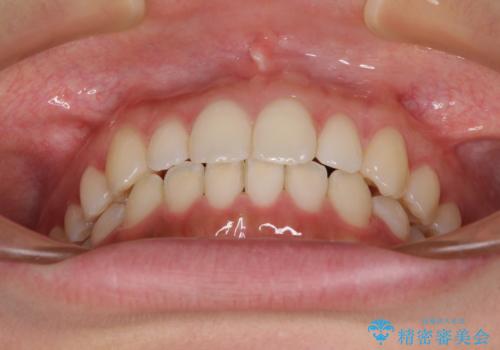

- 前歯のデコボコを気にして来院された患者様です。

通常であれば半年から10ヶ月程度で終了する歯並びでしたが、海外に長期出張することになったため、1年10ヶ月の期間を要しました。

出張に行かれてしまうと追加のマウスピースを発注できないため、マウスピースの交換頻度を低くし、一時帰国のタイミングに合わせていくことで、スムーズに進めて行くことができました。